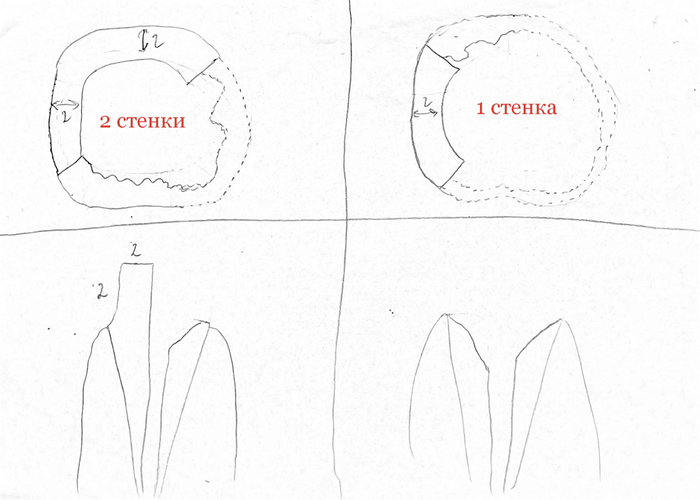

В главе 101 мы узнали, как восстанавливают зубы различной степени разрушенности и что такое феррул. Для тех, кто только пришел вкратце поясню. Феррул-это остаточная часть коронкового дентина высотой и шириной не менее 2 мм.

Если у нас остается менее 50% этого периметра, то зуб просто так не достроишь пломбой, не обточишь и не покроешь коронкой, иначе эта вся конструкция потом быстро окажется у пациента в руке из-за малой поверхности сцепления с зубом. Тут следует восстановить сперва культю штифтовой конструкцией, которая эту площадь знатно увеличит.

Штифты бывают нескольких видов.

Так выглядит изготовление конструкции. Картинки, просто взял в инете, если что.